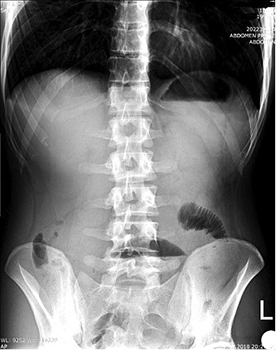

The plain radiograph showed signs of small bowel obstruction (Figure 1).